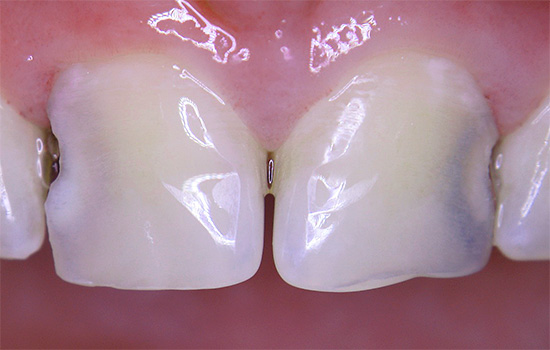

Nella foto: la carie in una fase iniziale di sviluppo:

Questo stadio di sviluppo della patologia è chiamato stadio del punto bianco: qui si verifica solo il danno iniziale allo smalto e la formazione di pori in esso sotto l'influenza di acidi aggressivi dalla cavità orale. Lo smalto perde la sua lucentezza, acquisisce un colore bianco più chiaro e saturo.

Ecco alcune altre foto di carie sul palco spot: